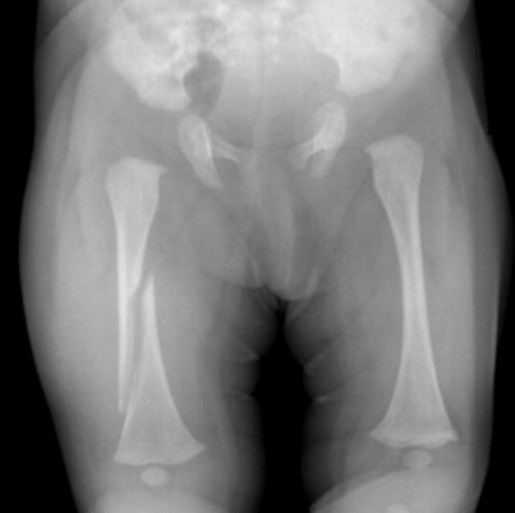

A 6-week-old infant is brought to your clinic with a swollen left thigh. The baby has been irritable for the last two days especially with diaper changes. You obtain the following radiograph.

What is the most likely diagnosis/etiology?

Femur fracture – likely inflicted injury (child abuse) but also consider OIIn addition to appropriate medical therapy, what else needs to be done at this point?

Notify MSW, CPS (DCS), law enforcement -